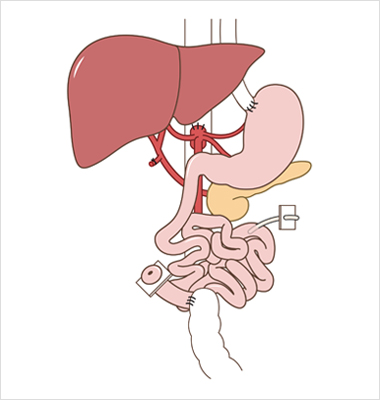

“장 자율성“ 을 획득하거나 경정맥영양으로 부터 독립하는 것

장부전 관리의 목표는 “장 자율성” 촉진을 통해 적절한 영양을 공급하고,

삶의 질을 개선하고, 이환율과 사망률을 낮추는 것

외과의사